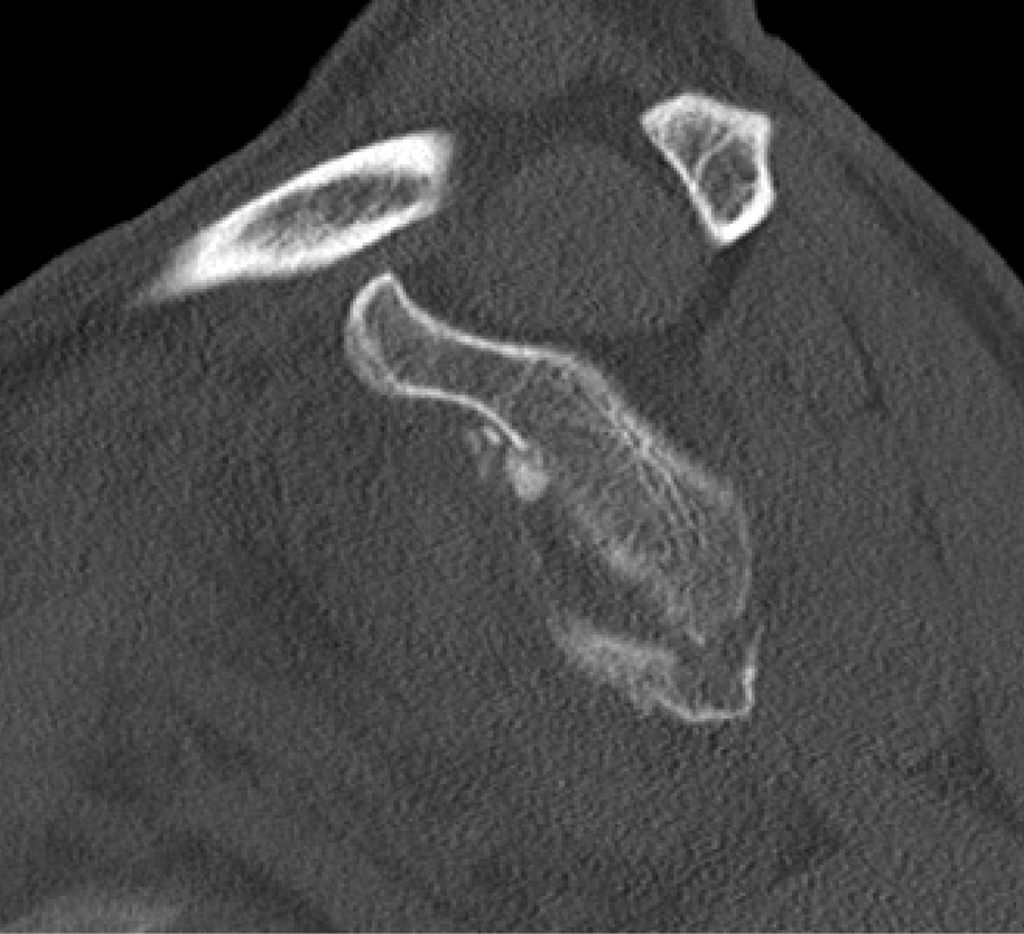

Die operative Versorgung ist indiziert bei instabilen Frakturen mit Subluxation des Humeruskopfes, großem knöchernem Defekt oder erheblichem Stufenversatz. Als Grenzwerte werden in der Literatur häufig eine Fragmentgröße von mehr als 20% der Glenoidfläche sowie ein Stufenversatz von über 5mm genannt (Itoi; Abb. 1 und 2).

Die arthroskopische Refixation hat sich als minimalinvasives Verfahren zur Versorgung selektierter Glenoidfrakturen etabliert. Insbesondere bei Ideberg-Typ-I-Frakturen (Ia ventral, Ib dorsal), knöchernen Bankart-Läsionen sowie kleinen bis mittelgroßen intraartikulären Fragmenten ermöglicht dieses Verfahren eine anatomische Rekonstruktion bei geringer Weichteilmorbidität. Voraussetzung ist das Vorliegen einer akuten Fraktur innerhalb eines Zeitraums von etwa zwei bis drei Wochen nach Trauma. Darüber hinaus müssen die Frakturfragmente reponierbar und von ausreichender Größe für eine stabile Fixation sein, während ausgedehnte Trümmerfrakturen oder eine relevante Schädigung des Skapulahalses ausgeschlossen sein sollten. Relative Kontraindikationen sind ausgeprägte Impressionen, chronische Frakturen mit Fragmentresorption sowie multidirektionale Schulterinstabilitäten. Eine sorgfältige präoperative Planung ist essenziell und basiert auf einer Computertomografie mit dreidimensionaler Rekonstruktion. Diese ermöglicht eine präzise Analyse der Fragmentgröße, der Dislokationsrichtung sowie des prozentualen Defektanteils der Glenoidfläche. Auf dieser Grundlage erfolgt die Festlegung der operativen Strategie, insbesondere die Wahl zwischen Schraubenosteosynthese und Fadenankerrefixation sowie die Planung der Anzahl und Position der arthroskopischen Portale.